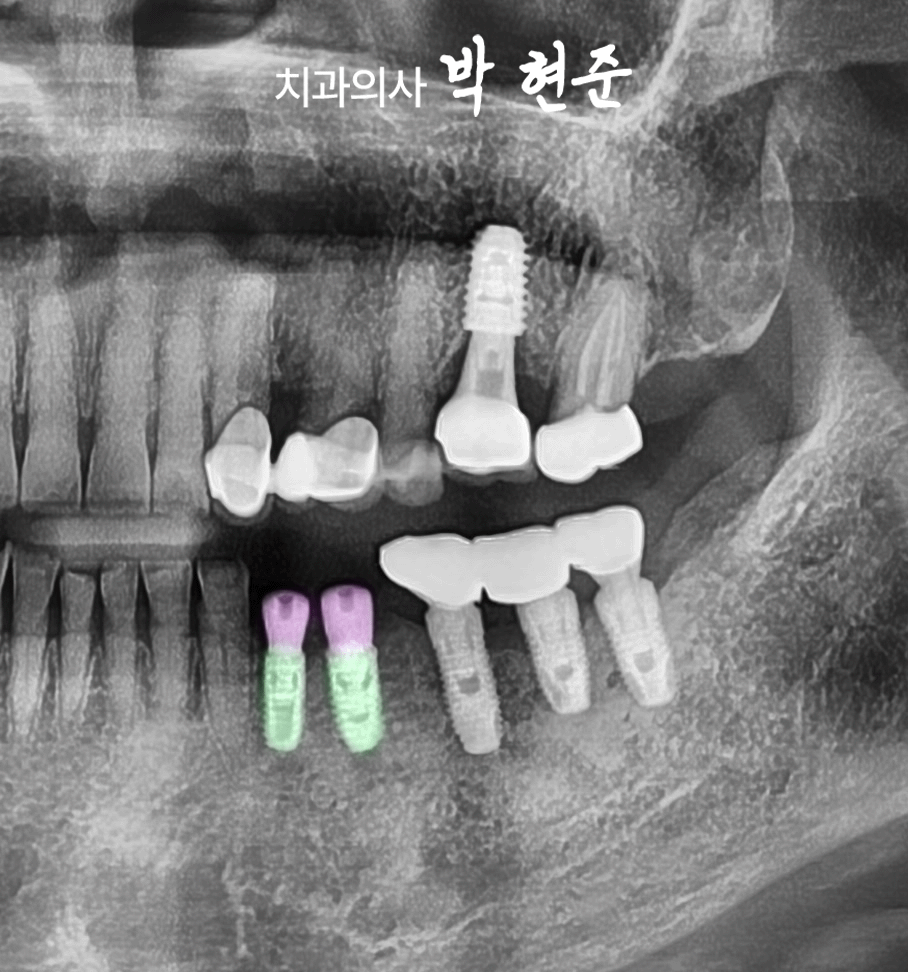

5. 최종 보철 연결

기간은 4개월 정도

소요되었습니다.

아무래도 픽스처가

치조골에 단단히 결합될 동안

기다리는 시간이 필요하기에

통상 하악은 3~4개월

상악은 3~6개월 정도

걸리는 것 같습니다.

2025.01.31

모란역 임플란트 가 모두 끝난

모습을 보겠습니다.

보철을 올릴 시기의

고정력은 80 이상으로

높은 수치가 나온 것을 확인하고

연결해 드렸으며

맞물리는 위쪽 송곳니의

저작력이 강하게 닿는듯하여

교합조정도 세밀히 해드렸습니다.